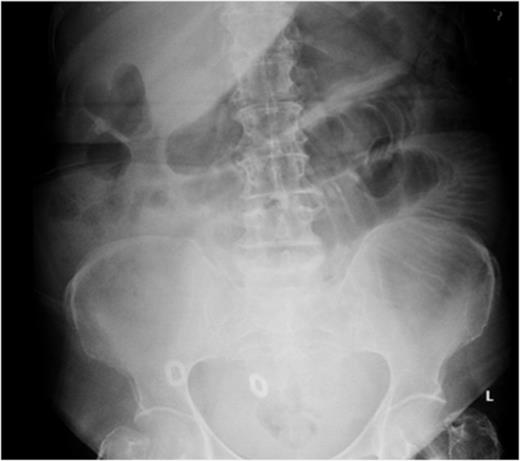

A CT scan was performed that showed dilation of the proximal small bowel, with a long segment of thickened small-bowel loops that was reported as possible intussusception (Fig. 2). The images were discussed further at the multidisciplinary surgical radiology meeting in the context of her haematology results. It was determined that the long segment of the thickened small bowel was, in fact, haemorrhage rather than intussusception.

Post-contrast CT (sagittal plane) showing proximal small-bowel dilation and a thickened small-bowel segment (Case 1).